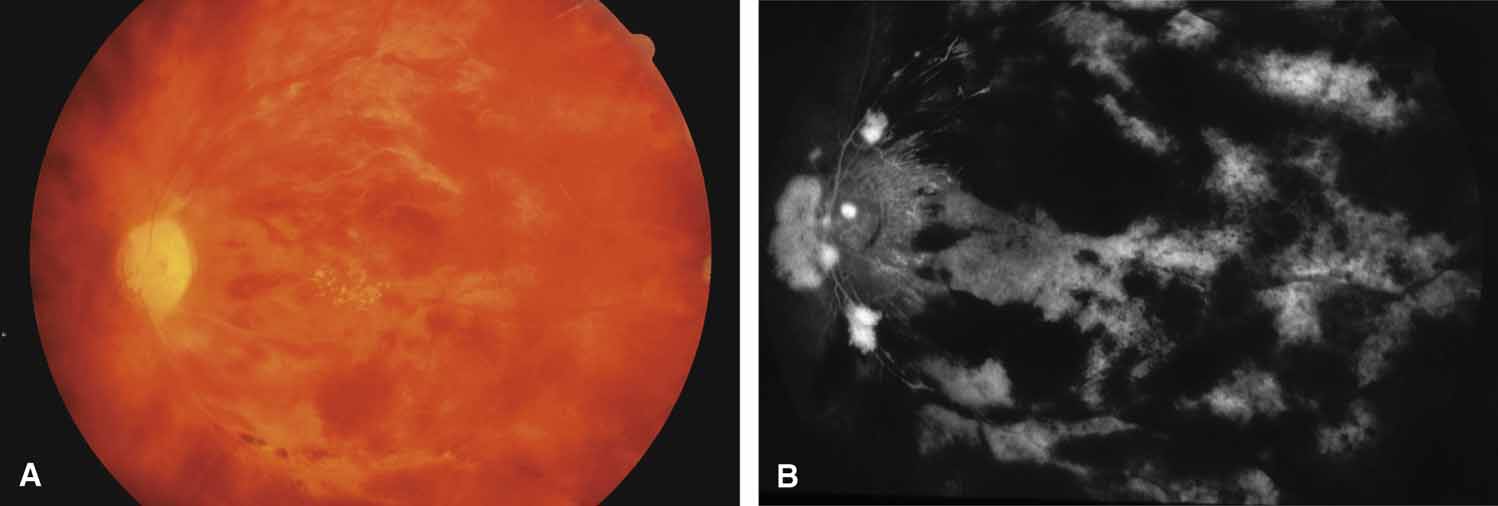

Rarely, an acute central retinal vein occlusion may produce choroidal congestion, ciliary body congestion, and rotation with transient peripheral iris angle narrowing and closure (Fig. 22) (see Table 6).123,124 This acute cyclocongestive glaucoma usually responds well to acetazolamide and cycloplegia.

Fig. 22 58-year-old female with acute CRVO. Several days after loss of vision, intraocular pressure elevated to mid 40s. A. Fundus appearance. B. Gonioscopic appearance with elevated pressure. Note loss of angle structures. C. Gonioscopic appearance after cycloplegic treatment. Angle structures are now visible. Intraocular pressure dropped to mid teens, where it has remained.